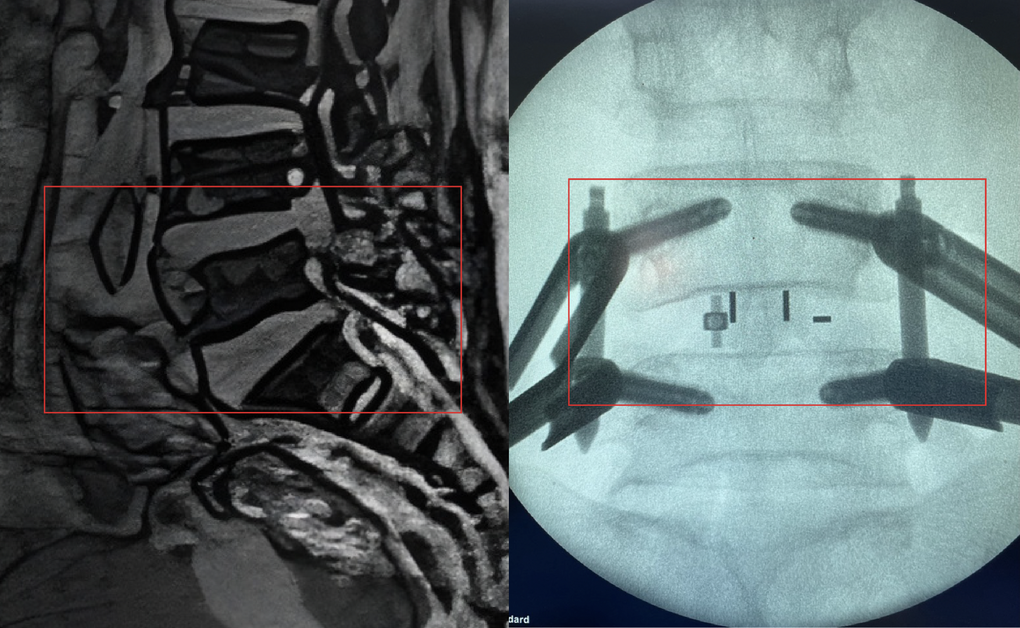

Dựa trên khám lâm sàng và chẩn đoán hình ảnh từ phim MRI, BS.CKII Lê Trọng Nghĩa, Phó Trưởng khoa Ngoại Thần kinh – Cột sống, nhận định bà B. bị hẹp nặng ống sống thắt lưng gây chèn ép rễ thần kinh hai bên L4–L5, do thoái hóa cột sống và dây chằng vàng, kèm thoát vị đĩa đệm L4-L5.

Dưới hướng dẫn của hệ thống C-arm hiện đại, hình ảnh X-quang được cung cấp theo thời gian thực ngay trong mổ, các bác sĩ chỉ cần một đường rạch nhỏ cạnh cột sống vùng L4-L5 để tiếp cận vị trí bị tổn thương bằng hệ thống ống nong vi phẫu. Các bác sĩ nhẹ nhàng cắt các mấu khớp và lấy nhân nhầy đĩa đệm thoát vị tại đốt sống L4-L5 nhằm giải phóng tủy sống và rễ thần kinh bị chèn ép.

Sau đó, ê-kíp đặt đĩa đệm nhân tạo sinh học có độ bền cao, tương thích tốt để tái tạo lại chiều cao cột sống, đồng thời ghép thêm xương tự thân của chính người bệnh, bắt 4 vít chuyên dụng sử dụng trong phẫu thuật xâm lấn tối thiểu dưới định vị của máy C-arm tích hợp sẵn trong phòng mổ.

Hai đốt sống L4-L5 được cố định chắc chắn, ngừa hiện tượng mất vững cột sống và giúp quá trình liền xương tốt hơn. Đặc biệt, thách thức trong ca mổ còn đến ở vấn đề đảm bảo an toàn gây mê và kiểm soát huyết động trên người bệnh có nguy cơ biến chứng phẫu thuật cao.

Hình ảnh đốt sống L4-L5 khi mới vào viện (bên trái) và sau khi bệnh nhân được phẫu thuật (Ảnh: BVCC).

Sau mổ, người bệnh không có dấu hiệu yếu liệt hay rối loạn cảm giác. Sau 3 ngày, bà B. tự đứng dậy và tự mình thực hiện những động tác tập đi lại đầu tiên. Đến ngày thứ 7, bà B. xuất viện trong tình trạng ổn định, vết mổ lành thương tốt, không nhiễm trùng và chảy máu sau mổ, không còn đau lưng, tê bì chi dưới.